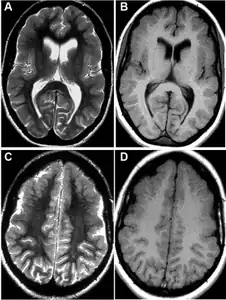

MRI-a,b,c,d)Developmental abnormalities/polymicrogyria in the frontal opercular cortex bilaterally -

Magnetic resonance imaging

MRI is one of the best techniques that can detect the lesions in the brain of the FCMS that some of the times are missed by just using a Computer-Tomography Scan. Also, this type of imaging can reveal right frontal lobes contusions encompassing the anterior operculum, the premotor area, and the association area.[10]